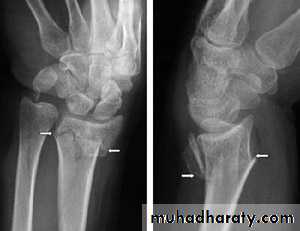

X-ray : a-p , lateral and oblique views are all essentials . Some time recent fracture show it self only in oblique view .

Usually the fracture is transverse and through the narrowest part of the bone (the waist) , but it could be in the proximal pole or in the tubercle ; few weeks after injury the fracture will be more obvious.

If union is delayed , cavitation appear on either side of the fracture .

In old ununited fracture there will be sclerosis at the edge and the appearance will be as there is extra carpal bone .Sclerosis of the proximal fragment is path gnomonic of avascular necrosis of the proximal fragment .